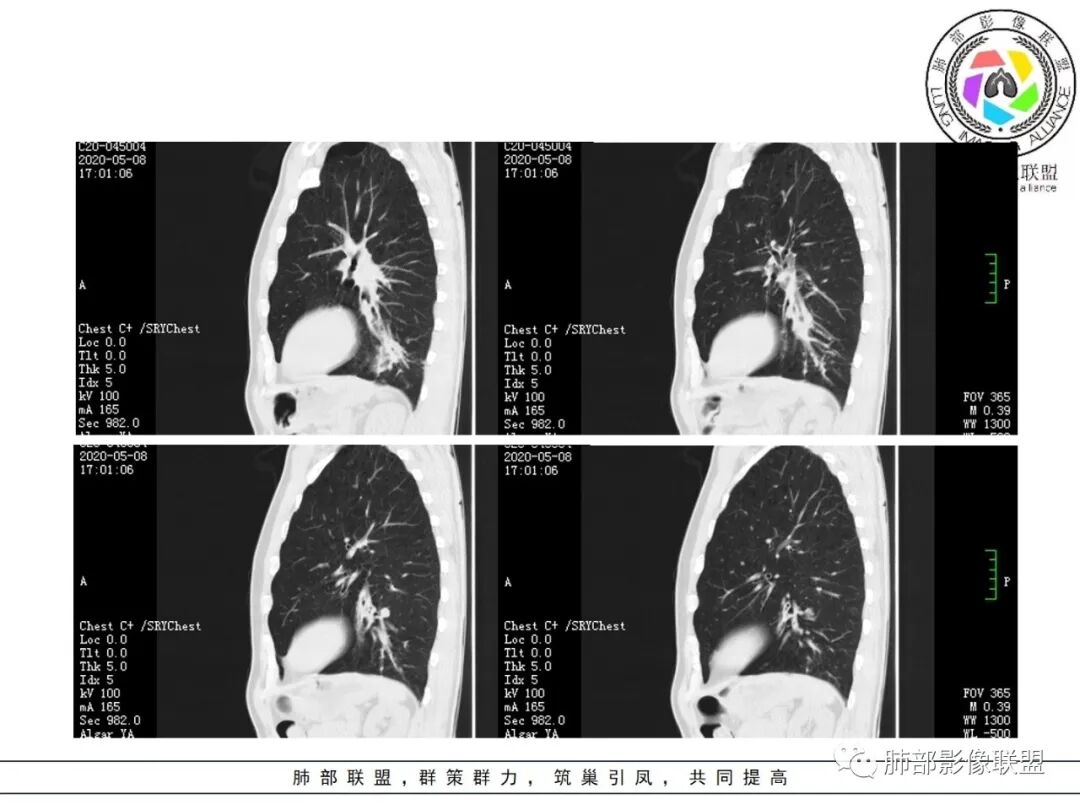

大雄:抗感染不吸收还是要警惕癌尤其主动脉旁的病灶红星:老年患者,咳嗽咳痰两个月,既往有糖尿病病史10年,左肺下叶后基底段斑片状、条索状、斑点状多形态的病灶,病灶内可见支气管征以及狭窄扩张的支气管影像。重建图像上可见到病灶沿支气管爬行。增强扫描病灶轻度强化,临近胸膜增厚。首先考虑感染性的病变,结核性的可能性最大。鉴别诊断上注意排除肺克以及淋巴瘤。三个石头:左肺下叶多发斑片,结节,条索,多态性?结核?多个结节边缘长毛刺,胸膜牵拉,分叶。矢状位支气管走行扭曲,没有完全阻塞,应该有粘液栓,有点像指状。主动脉旁病灶边缘平直,部分有鹏隆感,延迟强化。抗炎病灶变化不明显,结核?真菌?肿瘤也除外不了。没意见:左肺下叶基底段结节,膨隆、深分叶,毛刺,内侧串珠结节,中轴间质增厚,管腔狭窄,后基底段亚支不张,强化情况不明,考虑恶性,腺癌可能性大,另指套样征像,支气管壁增厚,不除外霉菌感染流心明智:老年患者,咳嗽咳痰2月。既往糖尿病史10年。胸CT:左肺下叶基底段多发结节影、斑片影、条索影,多数结节影沿支气管血管束分布,支气管壁厚,部分结节分叶、指状突,后基底段支气管狭窄闭塞。重建可见到病灶沿支气管爬行。增强扫描病灶明显强化,部分斑片影内可见低密度灶。普通抗感染无效。考虑:恶性病变,鳞?小?鉴别TB、隐球等。王秀仙:左肺下叶沿支气管血管束分布斑片、结节影,部分呈管状铸型生长,管腔狭窄,后基底段支气管阻塞,降主动脉旁不张实变,增强扫描病灶轻度强化,抗感染2周无吸收,考虑鳞癌。鉴别结核。蓝天白云:肺野内老年男性,咳嗽咳痰,有糖尿病病史,抗炎治疗无吸收。影像表现为左肺下叶支气管腔内结节影,支气管壁增厚,远侧小花小草,增强后实变影均匀强化,考虑鳞癌伴远端阻塞性炎症,鉴别结核。采莲:老年男性,咳嗽咳痰2月,有糖尿病史,左肺下叶沿支气管分布多发结节条状影,结节影不规则有分叶,成串珠样,靠下结节影成条索影,周围有空气储留,靠近主动脉不规则块状影,边缘平直,周围支气管壁增厚,支气管进入后阻塞,有糖尿病史,首选考虑炎性肺结核可能性大,鉴别肺鳞癌。了:左肺多发结节影,实性结节,,磨玻璃结节,左肺门结节影,深分叶,彭隆感,有血管滋养,考虑肿瘤,抗感染后病灶无吸收,感染不像,结节有强化,无卫星灶,结核可以排除不再涩的柠檬:老年男性,吸烟史,糖尿病史,咳嗽咳痰2月,抗感染2周无效。左下基底干及各分支管壁较弥漫增厚,伴支气管粘液栓,远端阻塞性肺炎,后基底段部分不张实变。先考虑感染病变,常规抗炎无效,需考虑结核、曲霉等,不能排除鳞癌合并感染,建议支气管镜检查。

尘缘:支气管壁增厚,沿支气管分布斑片状影,中远端支气管似堵塞,远端阻塞性改变,需要鉴别结核与肺癌,临床简单,镜检就行了。读片个人倾向于鳞癌伴感染吧。田园晚风:老年男性,有糖尿病史,咳嗽咳痰2月,左肺下叶沿支气管分布多发结节条状影,部分有分叶,成串珠样,靠下结节影成条索影,周围有空气储留,靠近主动脉不规则块状影,边缘平直,周围支气管壁增厚,支气管进入后阻塞,首选考虑肺癌可能性大,鉴别肺结核。

临床资料:老年男性,咳嗽咳痰2月余,慢性病史。有吸烟史40年(现已戒烟),抗感染治疗2周肺部病灶未见吸收。

影像所见:

支气管壁厚,支气管腔内高密度影填充。

2.关于支气管:上述病灶辖区外侧段支气管截断,环壁结节,远端阻塞性肺炎,是肺癌的重要征象。

支气管内膜结核,易导致支气管较长范围壁增厚,管腔不均匀狭窄甚至狭窄后扩张,也会引起远端肺组织相应的改变,如含气不良、液性潴留等,但较少出现树芽征或新旧不等结节影。支气管镜检有助于鉴别。